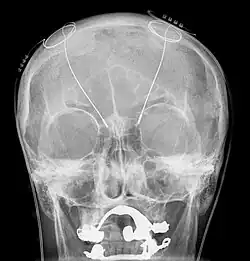

Van tevoren worden de hersenen nauwkeurig in beeld gebracht, bij voorkeur met een MRI-scan. De operatie begint met het aanbrengen van een raamwerk, een “frame” op de schedel. Vervolgens wordt er een CT-scan gemaakt van het hoofd met het frame. Door deze te combineren met de tevoren gemaakte MRI-scan, kan de computer precies berekenen op welke coördinaten de elektroden moeten komen. Tijdens het eerste deel van de operatie, het inbrengen van de elektroden, blijft de patiënt bij kennis. Door een opening die onder plaatselijke verdoving in de schedel wordt gemaakt, wordt de elektrode ingebracht. De elektrode heeft vier afzonderlijke contactpunten, zodat je op verschillende plaatsen in het geïmplanteerde hersengebied kunt stimuleren. Doordat de patiënt bij kennis is, kan door middel van proefstimulatie precies gezien worden wat het effect is en kan de plaatsing eventueel worden bijgesteld. Als de elektroden naar wens geplaatst zijn, wordt de patiënt onder narcose gebracht en kan de rest van de apparatuur worden ingebracht.

Het ingebrachte systeem bestaat uit drie onderdelen:

- De neurostimulator. Dit is een apparaatje dat batterijen in een behuizing van titanium bevat. Het wordt onder het sleutelbeen geplaatst en geeft stroompulsen af.

- De elektroden lopen door een gaatje in de schedel naar de plek in de hersenen, waar gestimuleerd wordt. De elektrode heeft vier platina stimulatiepunten en bestaat grotendeels uit polyurethaan.

- De geleidedraden die van de elektroden in het hoofd onder de huid, achter de oren langs, door de hals naar de neurostimulator gelegd worden.